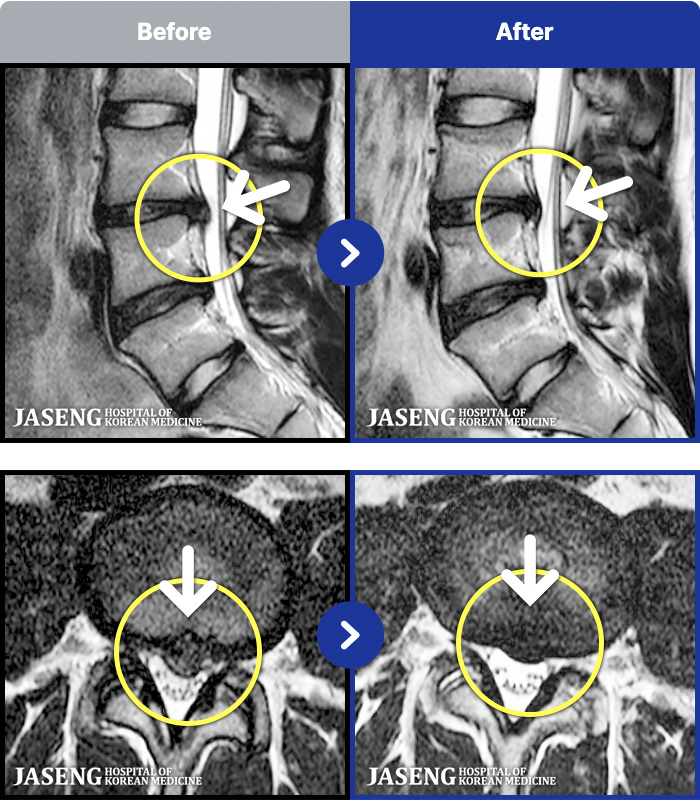

- MRI ġ

MRI ġ

1,237 MRI ũ ʸ Ȯϼ.